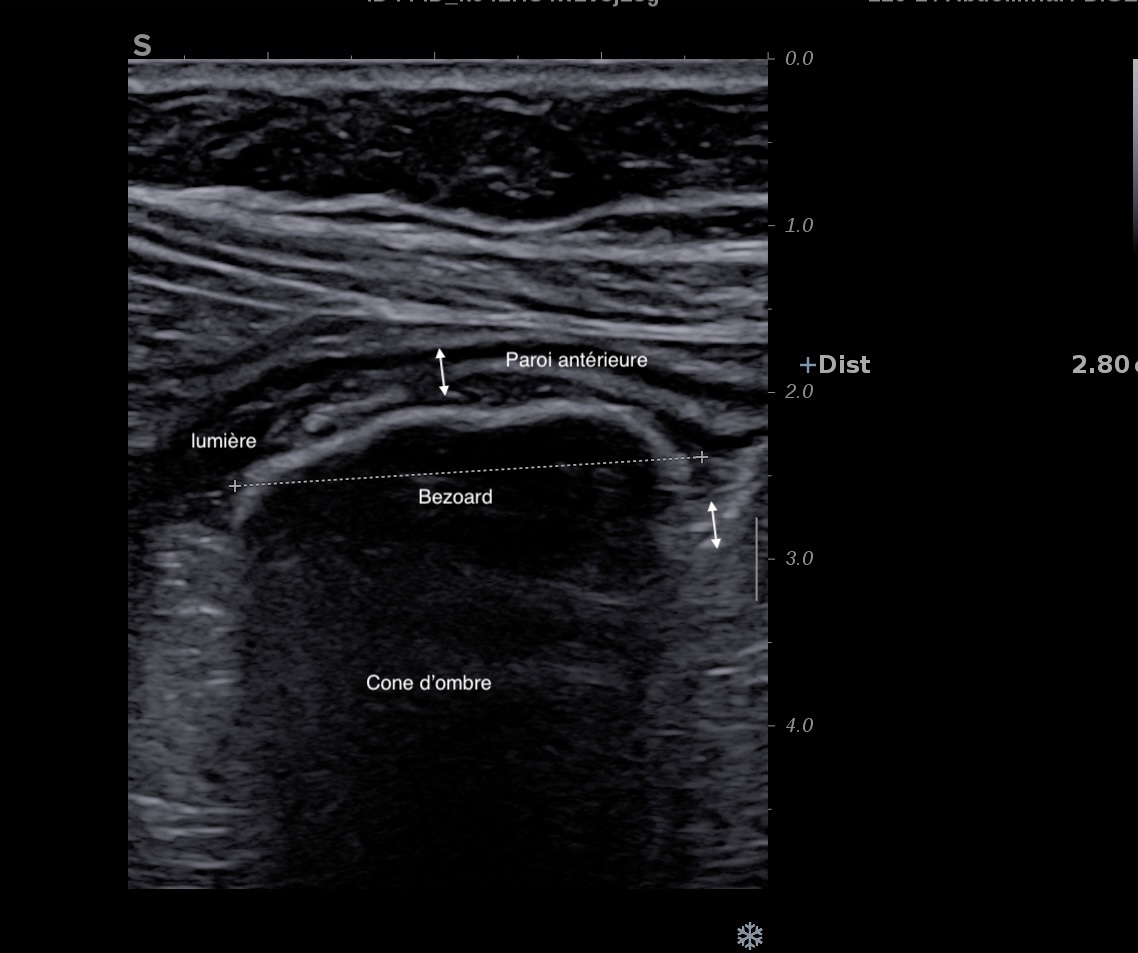

Présence d'un bézoard exceptionnellement, témoigne de la sténose

On peut voir en cas d'occlusion:

L'occlusion du grêle est très facile à voir en échographie